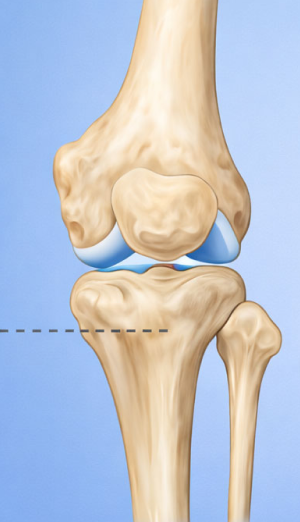

관절면과 평행하게 절골하여 각도를 교정

근위경골 절골술 교정 후

약간 벌리거나 닫아서 다리축을 “일자에 가깝게” 교정해서 닳은 안쪽 무릎의 부담을 줄이고 통증 감소 및 기능 향상을 유도합니다.